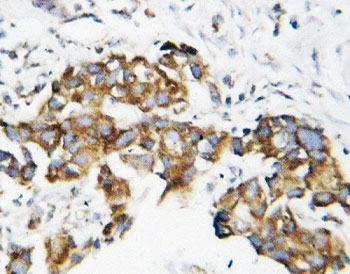

IHC-P: SOD1 antibody testing of human breast cancer tissue